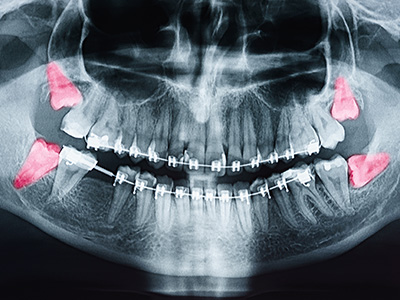

An impacted wisdom tooth is one that cannot fully emerge into its expected position, and clinicians identify impaction through a combination of clinical exam and imaging. During the exam, a dentist will check for swelling, gum coverage over the tooth, and signs of infection or damage to nearby teeth. Standard panoramic x-rays reveal tooth position and root anatomy, while three-dimensional imaging is reserved for complex cases that require more precise mapping of bone and nerve relationships.

Imaging also helps classify impactions as soft tissue or bony, and it shows the tooth's relationship to the mandibular nerve and sinus cavities. This information guides whether the tooth can be safely monitored or if removal is warranted to prevent future complications. A clear diagnosis reduces surprises and supports a more predictable treatment plan.

Panoramic radiographs are the most common initial imaging tool because they show the position of all third molars, root morphology, and relationships to adjacent structures. When a case is complex—such as close proximity to the mandibular nerve or an unusual root anatomy—three-dimensional cone beam computed tomography (CBCT) provides precise detail about bone contours, nerve pathways, and sinus relationships. This higher-resolution view supports safer surgical planning and helps predict potential complications.

Imaging also aids in monitoring teeth that are observed rather than removed, allowing clinicians to detect changes over time that would prompt intervention. Clear imaging reduces uncertainty and enables the dental team to explain risks and expectations in concrete terms. Informed planning contributes to smoother procedures and more predictable recoveries.